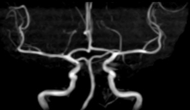

脳ドックで評価できるのは、無症候性脳梗塞(かくれ脳梗塞)、未破裂脳動脈瘤、脳腫瘍、そして認知症です。MRIやエコーに加えて、血液検査、心電図、神経学的診察では、動脈硬化や脳卒中を起こしうる不整脈(心房細動)、パーキンソン病や本態性振戦の有無が評価できます。

頭部MRI・頭部MRA・頚部MRA

頸動脈エコー検査